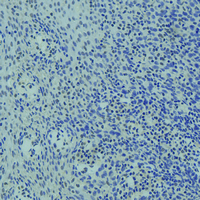

Immunohistochemical analysis of FOXO3 staining in human tonsil formalin fixed paraffin embedded tissue section. The section was pre-treated using heat mediated antigen retrieval with sodium citrate buffer (pH 6.0). The section was then incubated with the antibody at room temperature and detected using an HRP conjugated compact polymer system. DAB was used as the chromogen. The section was then counterstained with haematoxylin and mounted with DPX.